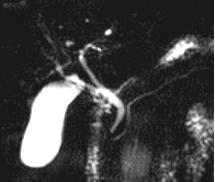

A normal MRCP showing the gallbladder, common bile duct, hepatic ducts, and pancreatic duct.